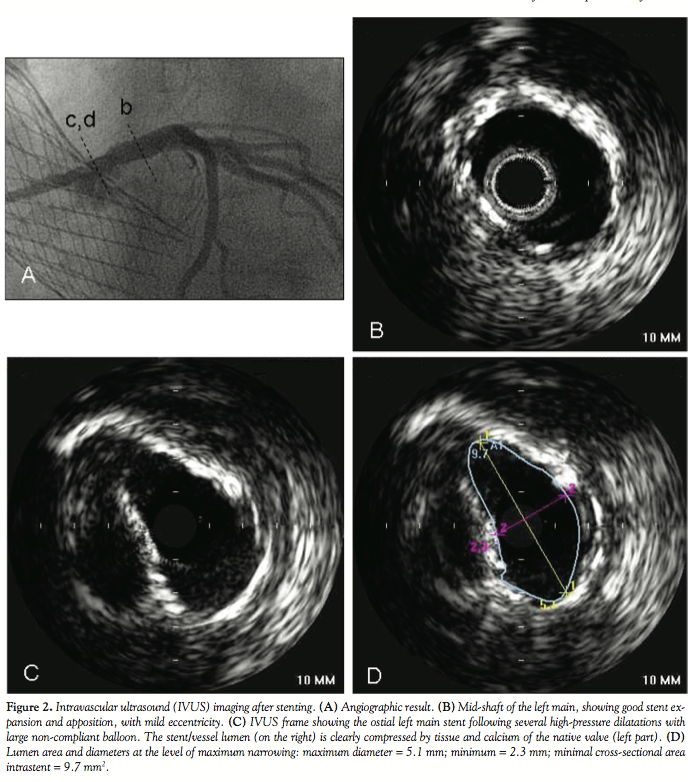

changes. On the basis of clinically suspicious and recurrent symptoms, we performed a coronary angiogram (Figure 1). Coronary angiography showed a severe stenosis of the left main trunk caused by the protrusion of a large calcium nodule of the native valve, which was compressed behind the bioprosthesis. We were not able to advance an intravascular ultrasound (IVUS) probe through the lesion at this stage. The patient was treated with a 3.5 x 8 mm stent, post-dilated

with a non-compliant 4.0 mm balloon inflated at very high pressure. Final IVUS examination is shown in Figure 2. A follow-up coronary angiography was planned after 4 months and Figure 3 summarizes angiographic and IVUS findings. There was clear recoil of the stent caused by external compression from the calcific native valve cusp, with an extreme lumen eccentricity documented by IVUS. In order to increase the radial force of the stent, we implanted a second stent within the previous one. Despite several high-pressure inflations with a non-compliant balloon, the final result was suboptimal (Figure 4). A second angiographic evaluation planned 9 months later confirmed the persistence of a mild narrowing of the left main ostium without significant neointimal hyperplasia.